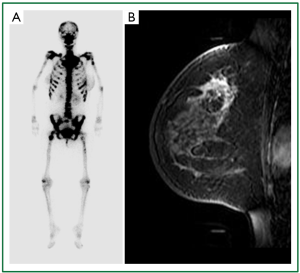

A 35-year-old woman was emergently admitted because of DIC (Table 1). Except for back pain and purpura on the legs, she did not have any physical abnormalities, even on her breasts. Because her condition suggested the presence of hematologic disease, bone marrow aspiration cytology was performed, and a few nests of adenocarcinoma were detected (Figure 1). A bone scintigram showed a so-called “beautiful bone” finding (Figure 2A), suggesting massive involvement of the bone. The elevation of breast cancer-related tumor markers (Table 1) suggested the presence of breast cancer with bone marrow dissemination. Therefore, radiological examinations were performed for detecting breast cancer. Magnetic resonance imaging (MRI) revealed an enhanced area in the upper-outer quadrant of the left breast (Figure 2B), although the findings of mammography and ultrasonography were not definitive. A core needle biopsy was performed on her left breast; examination of the biopsy specimen revealed invasive ductal carcinoma that was estrogen receptor-negative, progesterone receptor-negative, and HER2-negative (Figures 3,4). On the basis of these findings and her hematologic condition, weekly administration of paclitaxel (80 mg/m2) was chosen as the treatment. The clinical course of this case is summarized in Figure 5. Chemotherapy was performed along with treatments for DIC, including platelet transfusion. After 6 cycles of paclitaxel treatment, she recovered from DIC and was discharged from the hospital. The CA15-3 level, which had dramatically decreased after treatment, started to increase again during paclitaxel treatment. After 10 weeks, the patient complained of dyspnea. A chest radiograph revealed that the disease had recurred as lymphangitis carcinomatosa in the lung. Because the hematological conditions had been completely restored, a combined therapy of epirubicin (90 mg/m2) and cyclophosphamide (600 mg/m2) (EC) was administered. EC improved her respiratory function dramatically and was administered for 4 cycles. Twenty-three weeks after treatment, she developed a spike fever and liver dysfunction accompanied with jaundice. Worsening liver metastases were the most likely causes of cholangitis, because computed tomography (CT) revealed the appearance of a mass lesion in the left lobe of the liver. Dissemination in the liver had been suspected because of the constant elevation of transamylases since admission. We decided that EC was effective for the treatment of disease in the lung but not in the liver; therefore, vinorelbine (40 mg/m2) was chosen as the next regimen. Laboratory data showed that the liver function dramatically improved after 4 cycles of treatment. After 27 weeks, the respiratory function worsened again with a recurrence of lymphangitis carcinomatosa. Although rechallenge with EC improved dyspnea, the adverse effects of this treatment, including leukocytopenia, were too severe to continue this regimen. A combination of capecitabine and cyclophosphamide was started as an alternative therapy. Liver dysfunction progressed gradually. The patient died of liver failure after 33 weeks of administration of therapy.